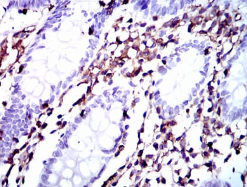

MSN Mouse Monoclonal antibody[2C1C4]

Moesin (for membrane-organizing extension spike protein) is a member of the ERM family which includes ezrin and radixin. ERM proteins appear to function as cross-linkers between plasma membranes and actin-based cytoskeletons. Moesin is localized to filopodia and other membranous protrusions that are important for cell-cell recognition and signaling and for cell movement.

IHC    1/200 - 1/1000